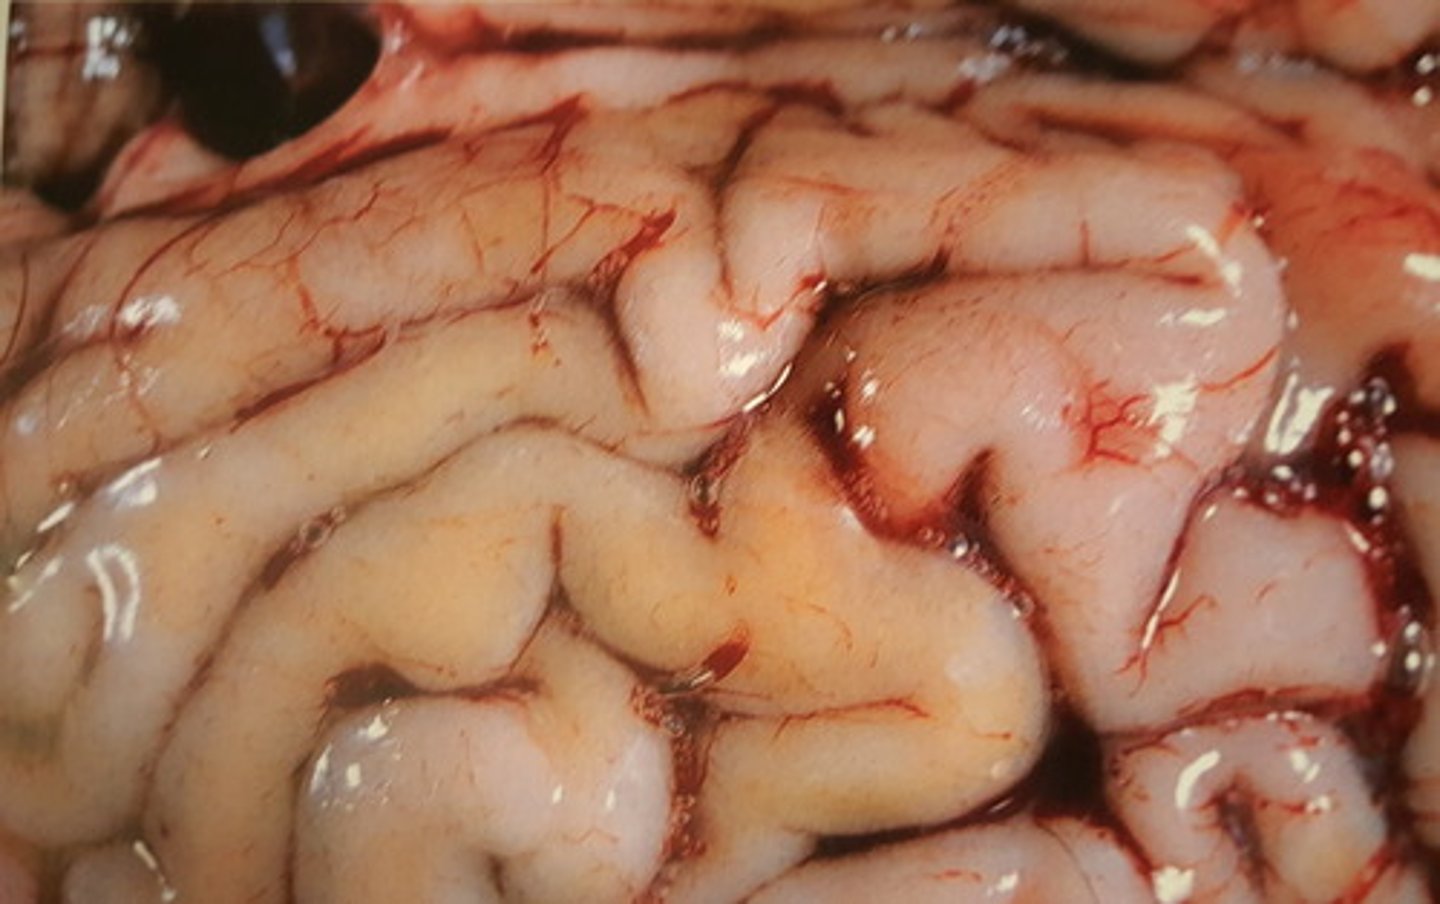

akut, diffus leptomeningitis.

Inflammation karakteriseret med ødem og hyperæmi

Hjerne fra okse. Patoanatomisk diagnose?

akut, stedvis diffus, fibrinopurulent leptomeningitis

Hjerne fra okse. Patoanatomisk diagnose?

akut diffus purulent leptomeningitis.

Septikæmi med E. coli

Hjerne fra okse. Patoanatomisk diagnose? Ætiologi?